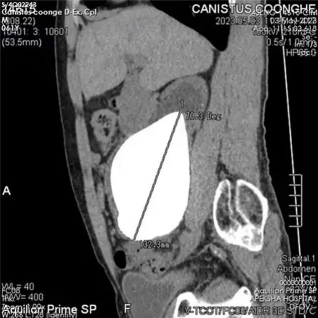

图2 患者肾结石影像图片(图源:网络)

图1 外科医生Kugadas Sutharshan博士取出了一块 长13.37厘米,宽10.55厘米的肾结石(图源:网络)

近日,斯里兰卡62岁的退伍士兵Canistus Coonghe,在科伦坡陆军医院进行了一次大手术,移除了世界上最长、最重的肾结石。这颗肾结石长度达到了13.37厘米(正常男性肾脏为10-12厘米),重量为801克,是普通成年男性肾脏重量的5倍以上,成功打破了最长肾结石和最重肾结石的两项吉尼斯世界纪录。先前最重肾结石的记录是2008年巴基斯坦男子创造的616克(1.36磅)。而最长的肾结石测量长度为5.11英寸(13厘米),于2004年从印度男子身上手术取出。

外科医生Kugadas Sutharshan博士表示:“患者自述,2020年以来一直感到腹痛,吃药也无济于事。通过检查我们发现患者体内存在巨大的肾结石,而且这颗葡萄柚大小的肾结石位于患者右肾中,但器官功能正常。”